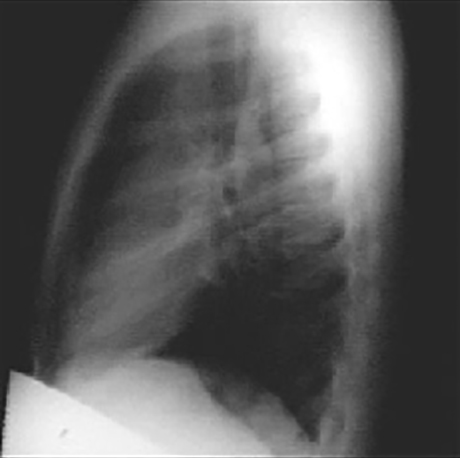

The lateral view shows a dilated ascending aorta as evidenced by the shadow anterosuperior to the heart.